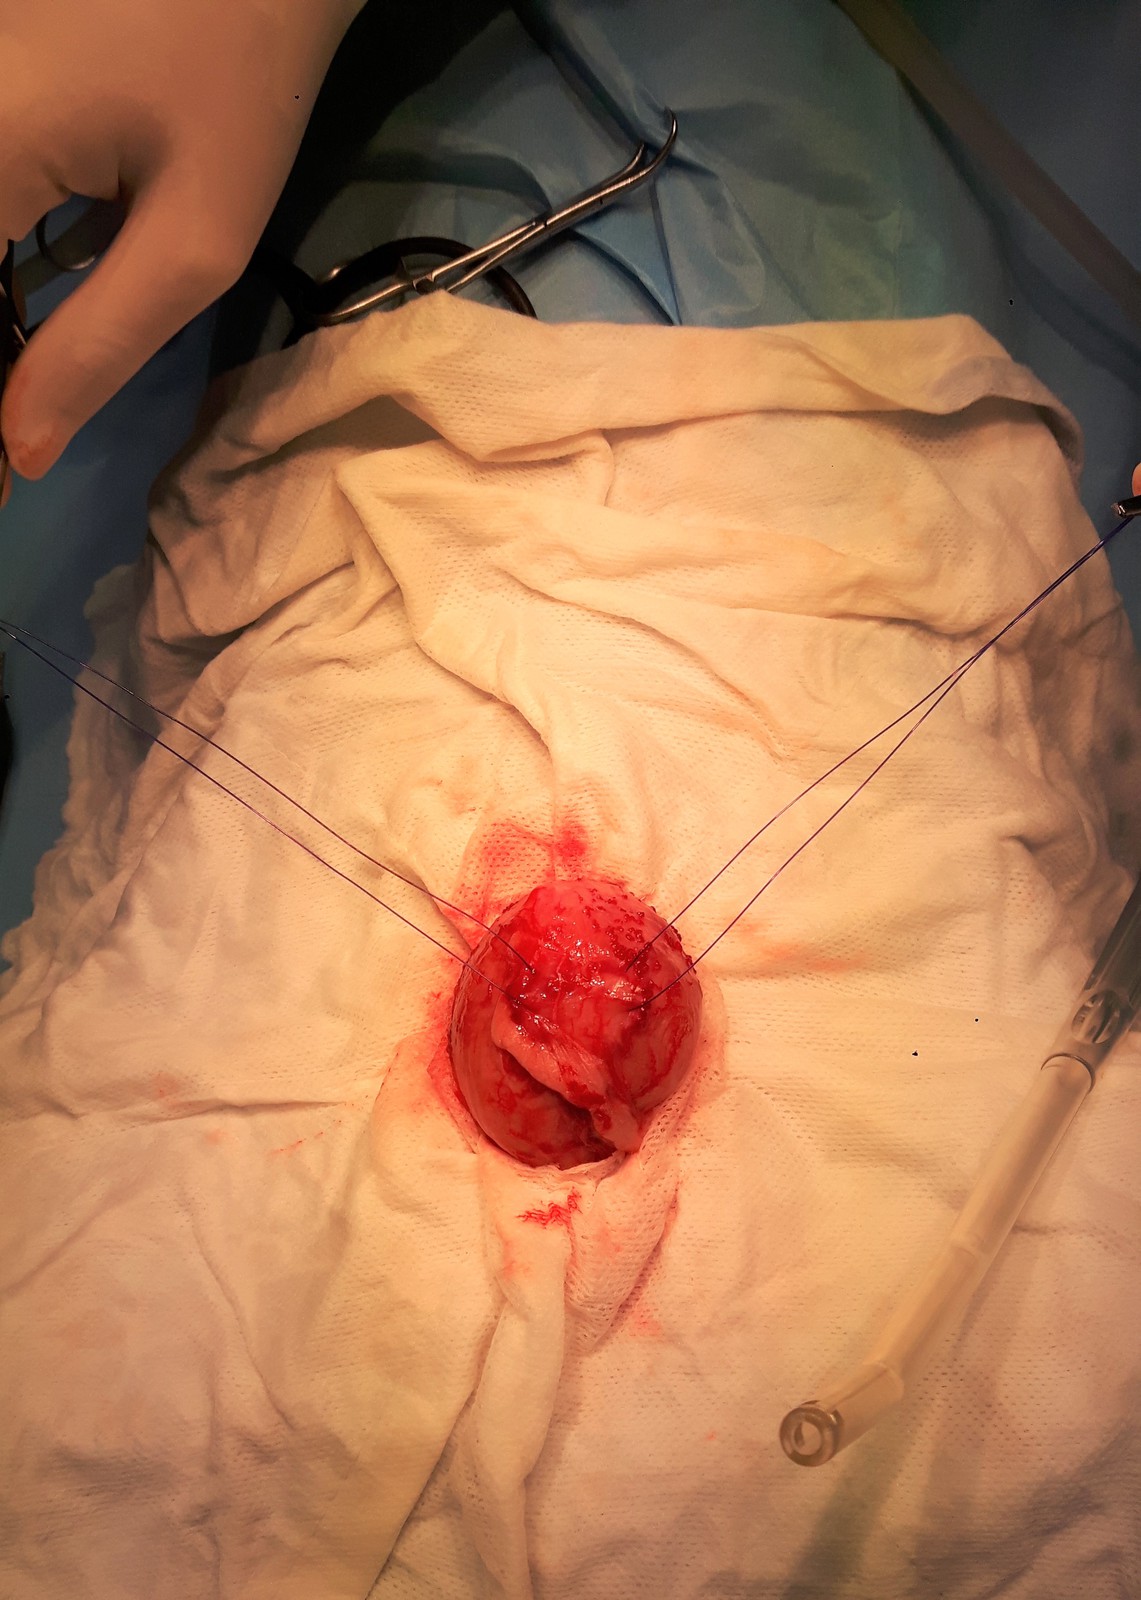

Po otevření dutiny břišní jsme odrouškovali močový měchýř, který byl palpačně zcela vyplněný drobnými urolity.

20170704_140605.jpgCystotomie 1.jpgCystotomie 2.jpg

Po otevření močového měchýře jsme nejprve excidovali kousek sliznice, kterou jsme společně s močí získanou cystocentézou a částí sterilních cystolitů odeslali na bakteriologickou kultivaci. Až poté jsme aplikovali Agáthě nitrožilně peroperační ATB clonu (cefazolin), abychom neovlivnili výsledek kultivace.

Dále následovalo „nekončící“ vytahování a retrográdní i normográdní vyplachování lumen močového měchýře a uretry, abychom po sobě v močovém měchýři ani v uretře nezanechali jediný kamínek.

Poté jsme standardně uzavřeli cystotomickou ránu, provedli omentalizaci stěny měchýře a uzavřeli dutinu břišní, podkoží a kůži.

Cystotomie 3.jpgCystolity 1.jpg Cystotomie 4.jpg